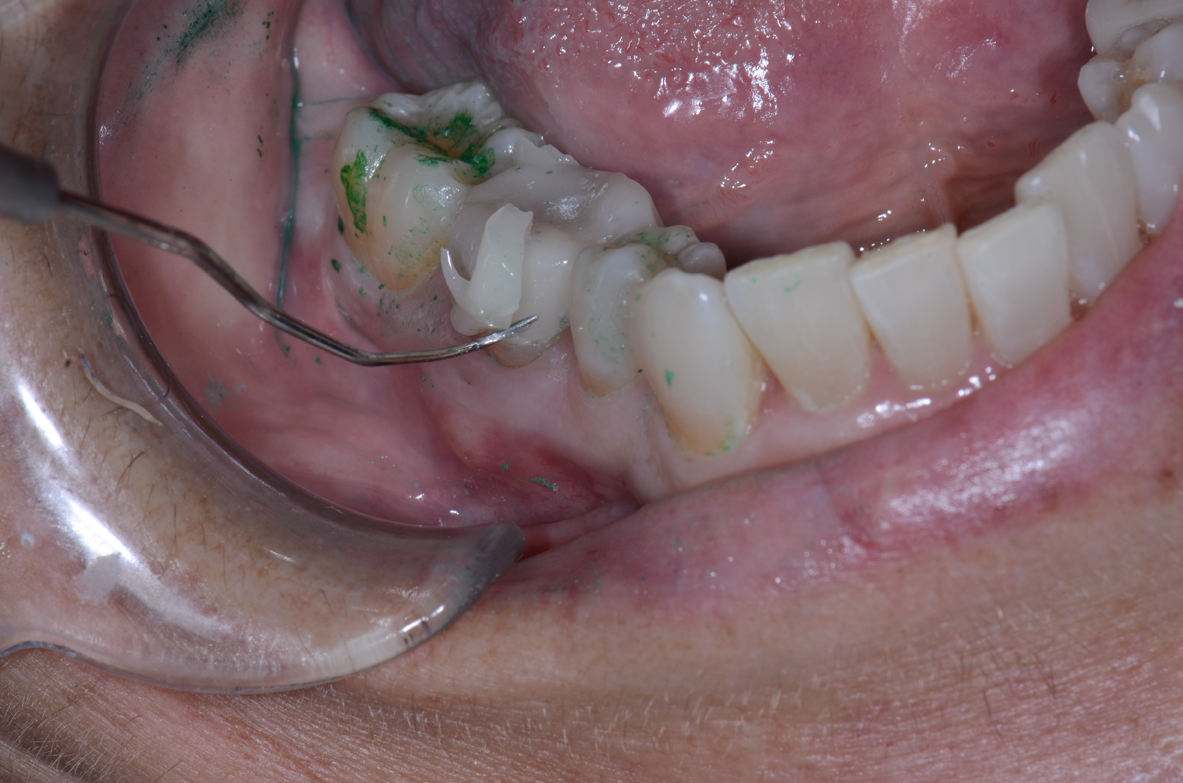

3. Apply pressure and use an explorer to determine whether or not the provisional is fully seated. Cure the material with an LED curing light for no more than one to two seconds from the lingual and repeat on the buccal. The material will now peel off easily and excess can be removed with an explorer or scaler (Figs. 12-15).

Fig. 13 Fig. 14 Fig. 15

4. Floss the contacts to remove excess that is wedged interproximally. Using your light-curing unit, cure for 20 seconds from the buccal and then again on the lingual. This will increase the translucency and the set of the material. The chemical cure time of the cement is six to seven minutes intraorally. A final light curing facilitates easy and efficient cleaning of the excess while increasing the initial cure. The set of the material is sufficient to rinse the patient, sit them up to deliver post-op instructions and ultimately release them.